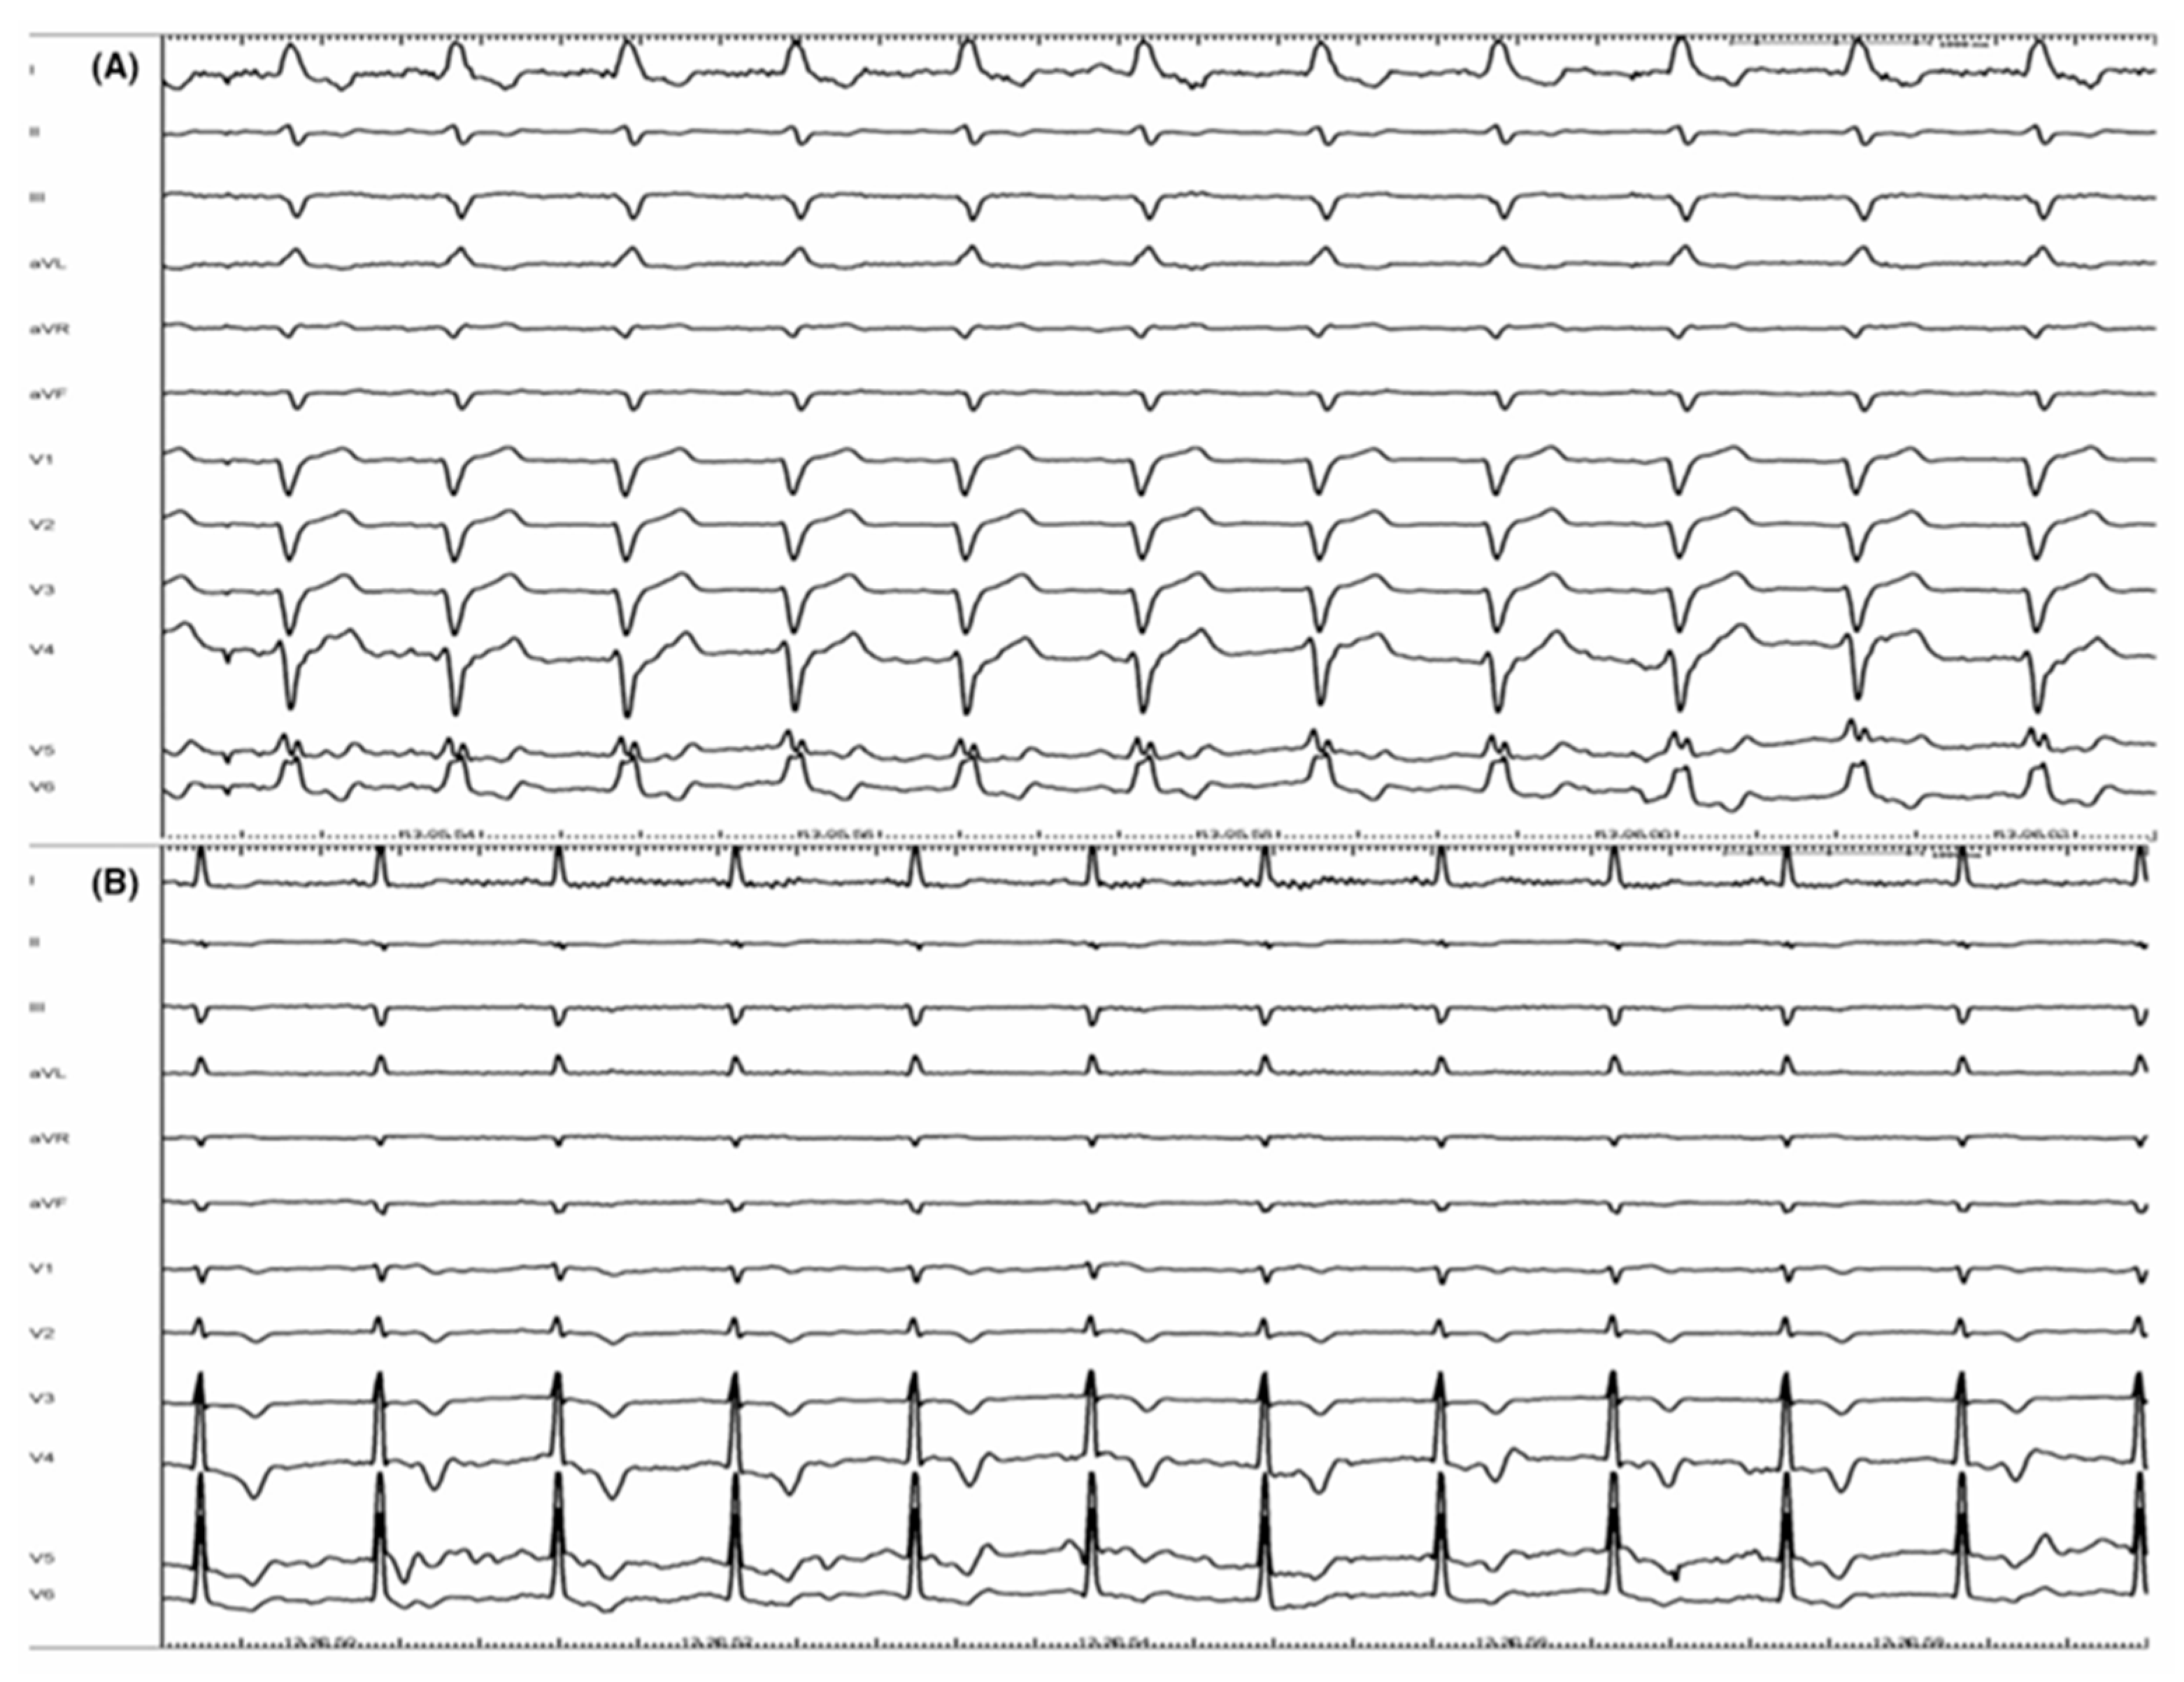

To overcome the CRT’s limitations, physiological pacing (of the His bundle or the left branch area) has established itself as a support for CRT. His bundle pacing, in some cases, can itself correct the left bundle branch block [66] (Figure 1). In the HOT-CRT trial, His–Purkinje conduction system pacing was used in patients with heart failure, and a coronary sinus (CS) lead was added only if His pacing resulted in incomplete electrical resynchronization. This strategy resulted in a greater change in LVEF compared with the CRT approach only [67].

Figure 1.

Correction of complete left bundle branch block (CLBBB): panel (A) shows a basal ECG with CLBBB. Panel (B) represents the ECG from the same patient at the end of procedure. CLBBB has been completely corrected by a selective His bundle pacing (HBP) (with permission by Scarà et al. [61]).